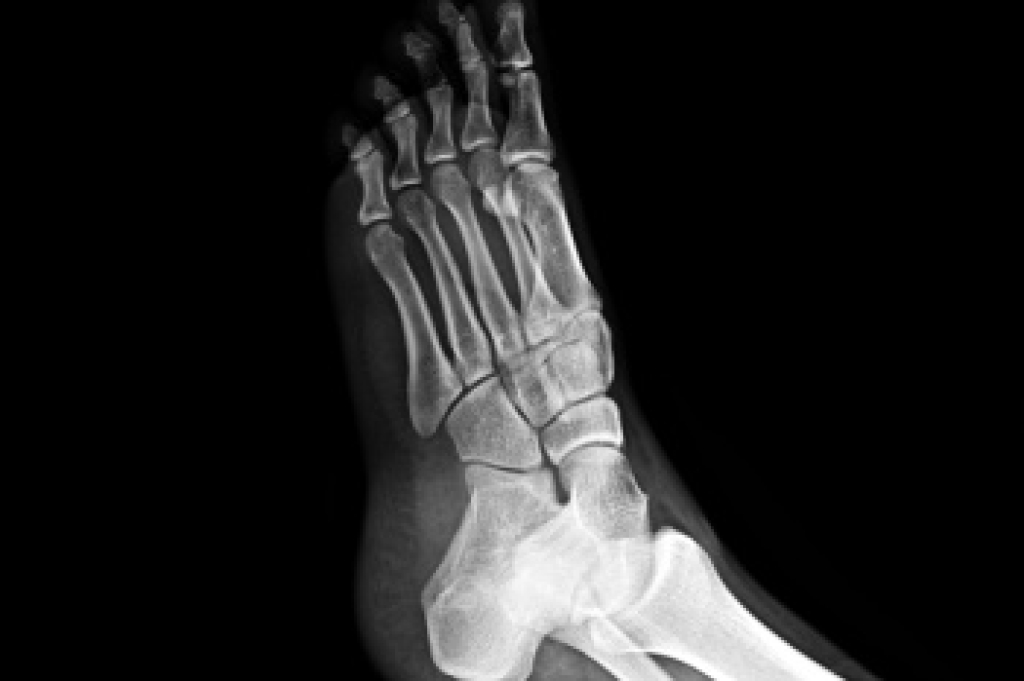

Causes and Risks of Foot Stress Fractures

Stress fractures in the feet are hairline cracks in the bone that often develop from repetitive force, rather than a single traumatic event. Stress fractures generally occur in the long bones of the foot, which endure significant impact during walking, running, and jumping. Overtraining, sudden increases in activity, or inadequate rest between workouts raise the risk. Foot structure also plays a role, with flat feet, high arches, or rigid arches contributing to uneven distribution of pressure that can stress certain bones. People with osteoporosis or low bone density are at higher risk, and nutritional deficiencies, such as inadequate calcium or vitamin D, may weaken bone strength. A podiatrist can confirm a diagnosis through examination and imaging, recommend appropriate footwear or orthotics, and advise whether surgery is required in severe cases. If you have symptoms of stress fractures in your feet, it is suggested that you make an appointment with a podiatrist for an exam, diagnosis, and treatment.

How Are They Caused?

Stress fractures are the result of repetitive force being placed on the bone. Since the lower leg and feet often carry most of the body’s weight, stress fractures are likely to occur in these areas. If you rush into a new exercise, you are more likely to develop a stress fracture since you are starting too much, too soon. Pain resulting from stress fractures may go unnoticed at first, however it may start to worsen over time.

Stress fractures do not always heal properly, so it is important that you seek help from a podiatrist if you suspect you may have one. Ignoring your stress fracture may cause it to worsen, and you may develop chronic pain as well as additional fractures.